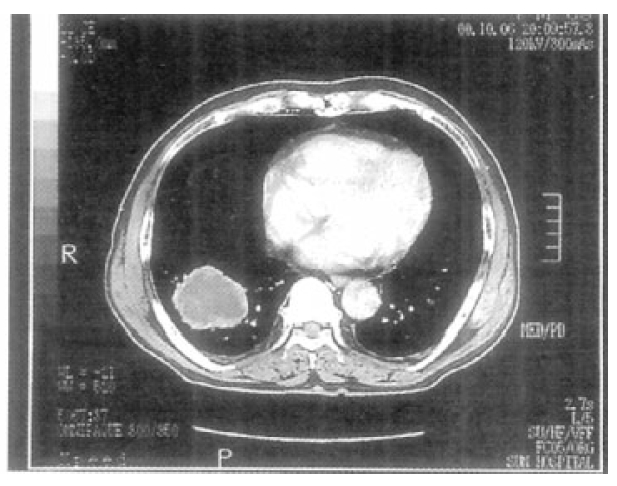

The laboratory tests were as follows: WBC count, 15.7×103/uL with 78% neutrophils, 13% lymphocytes, 7% monocytes, 1% eosinophils and others 1%; Erythrocyte sedimentation rate, 44 mm/h; hemoglobin, 14.4 g/dL; hematocrit, 41.4%; platelet count, 313×103/uL. Other laboratory findings including liver function, blood glucose level, renal function, electrolytes and urine microscopy, were all within normal limits. Arterial blood gas analysis on room air revealed a pH of 7.459, Pco2 of 36.8 mmHg and Po2 of 76.9 mmHg. The chest radiograph obtained at the time of admission showed a round mass in the right lower lobe (Figure 1). The chest CT scan performed at the referring hospital confirmed the presence of a 4×4 cm-sized, smoothly marginated, soft tissue density with central lower density in the right lower lobe.

Figure 1.

The chest PA shows a round mass with central low density in the right lower lobe.